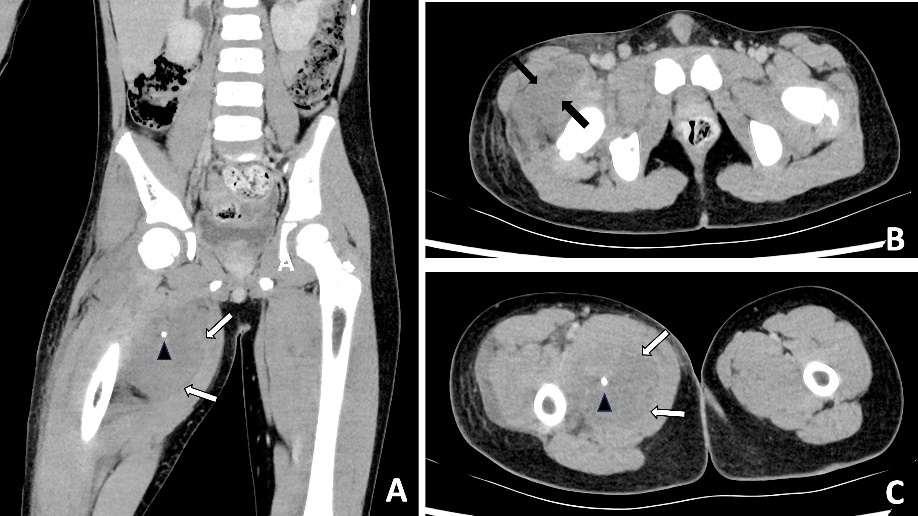

Blood results revealed a high white blood cell count (30.3 × 109/L) with neutrophilia and high C-reactive protein (245.2 mg/L). An X-ray of the hip was performed and interpreted as normal, although in retrospect, phleboliths were present in the region of the adductor muscles (Figure 1). Abdominal CT was normal. Fat stranding, soft tissue swelling and possible fluid collections were identified within the anterior and medial thigh on CT. Retrospectively, there were also multiple intramuscular phleboliths within the adductor muscles (Figure 2).

In retrospect, the presence of intramuscular phleboliths on CT in the cases presented above was the best clue to the diagnosis of an infected VM. Phleboliths occur in approximately 30 per cent of VMs.15 Intramuscular phleboliths have a limited imaging differential diagnosis and are generally taken to be pathognomic of VM.16 Radiologist and clinician awareness of this rare presentation of VMs is important; if intramuscular phleboliths are identified, the diagnosis of VM should be raised and the use of MRI may further assist in the diagnosis. If clinical doubt remains in an acutely unwell patient, prompt surgery to exclude necrotising soft tissue infection is prudent.

Timely surgical exploration is indicated in septic patients where necrotising soft tissue infection cannot be excluded. However, it is important to consider rare conditions that may present similarly, such as infected VMs. The presence of intramuscular phleboliths on CT, especially in a child, is the best imaging clue to this unusual diagnosis and should not be overlooked.